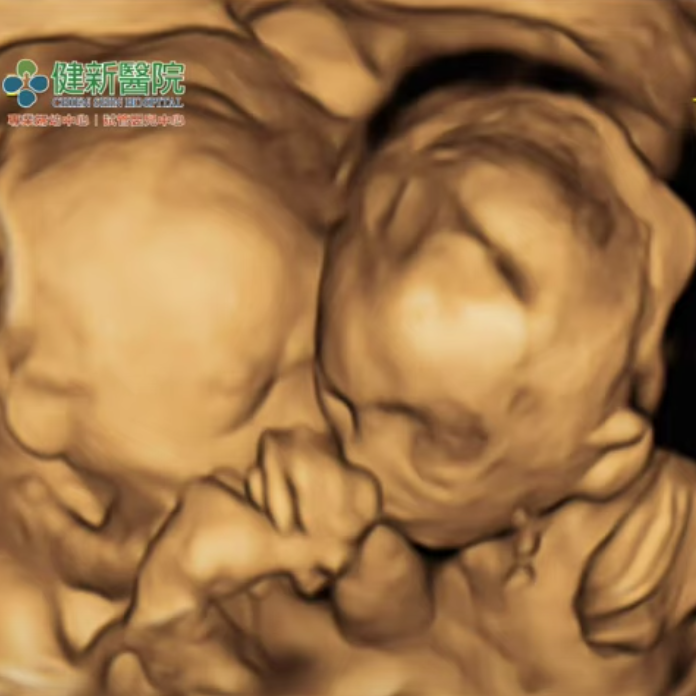

健新醫院寶寶超音波-雙胞胎親臉頰“ 我們與妳一樣關心寶寶健康,『四階段高層次超音波』